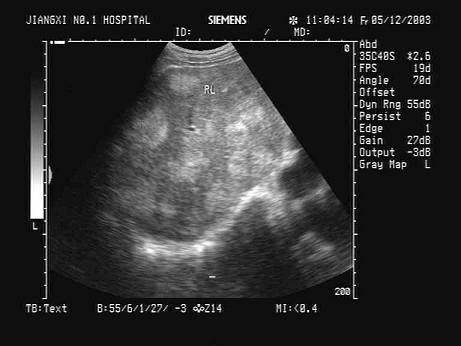

问题 某患者,男,45岁,肝区不适,肝功能异常。行超声检查如图,诊断为?(?)

选项 A.弥漫性肝癌 B.结节状肝硬化 C.多发性血管瘤 D.血吸虫肝 E.不均匀性脂肪肝

答案 A